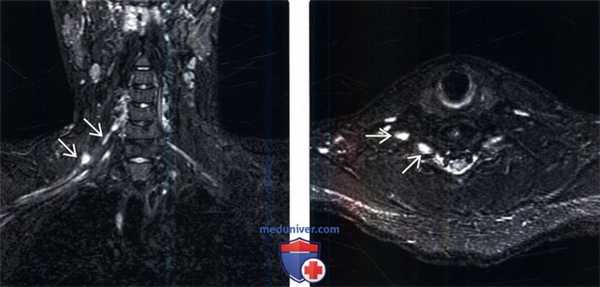

(Слева) На фронтальном STIR МР-И, пациент с сочетанным проникающим и тракционным повреждением правого плечевого сплетения в результате огнестрельного ранения: признаки полного пересечения С6 ветви плечевого сплетения. Признаков псевдоменингоцеле вследствие отрыва корешка не определяется.

(Справа) Аксиальный срез, STIR МР-И, этот же пациент: патологическое утолщение и гиперинтенсивность Т2-сигнала поврежденных элементов правого плечевого сплетения.